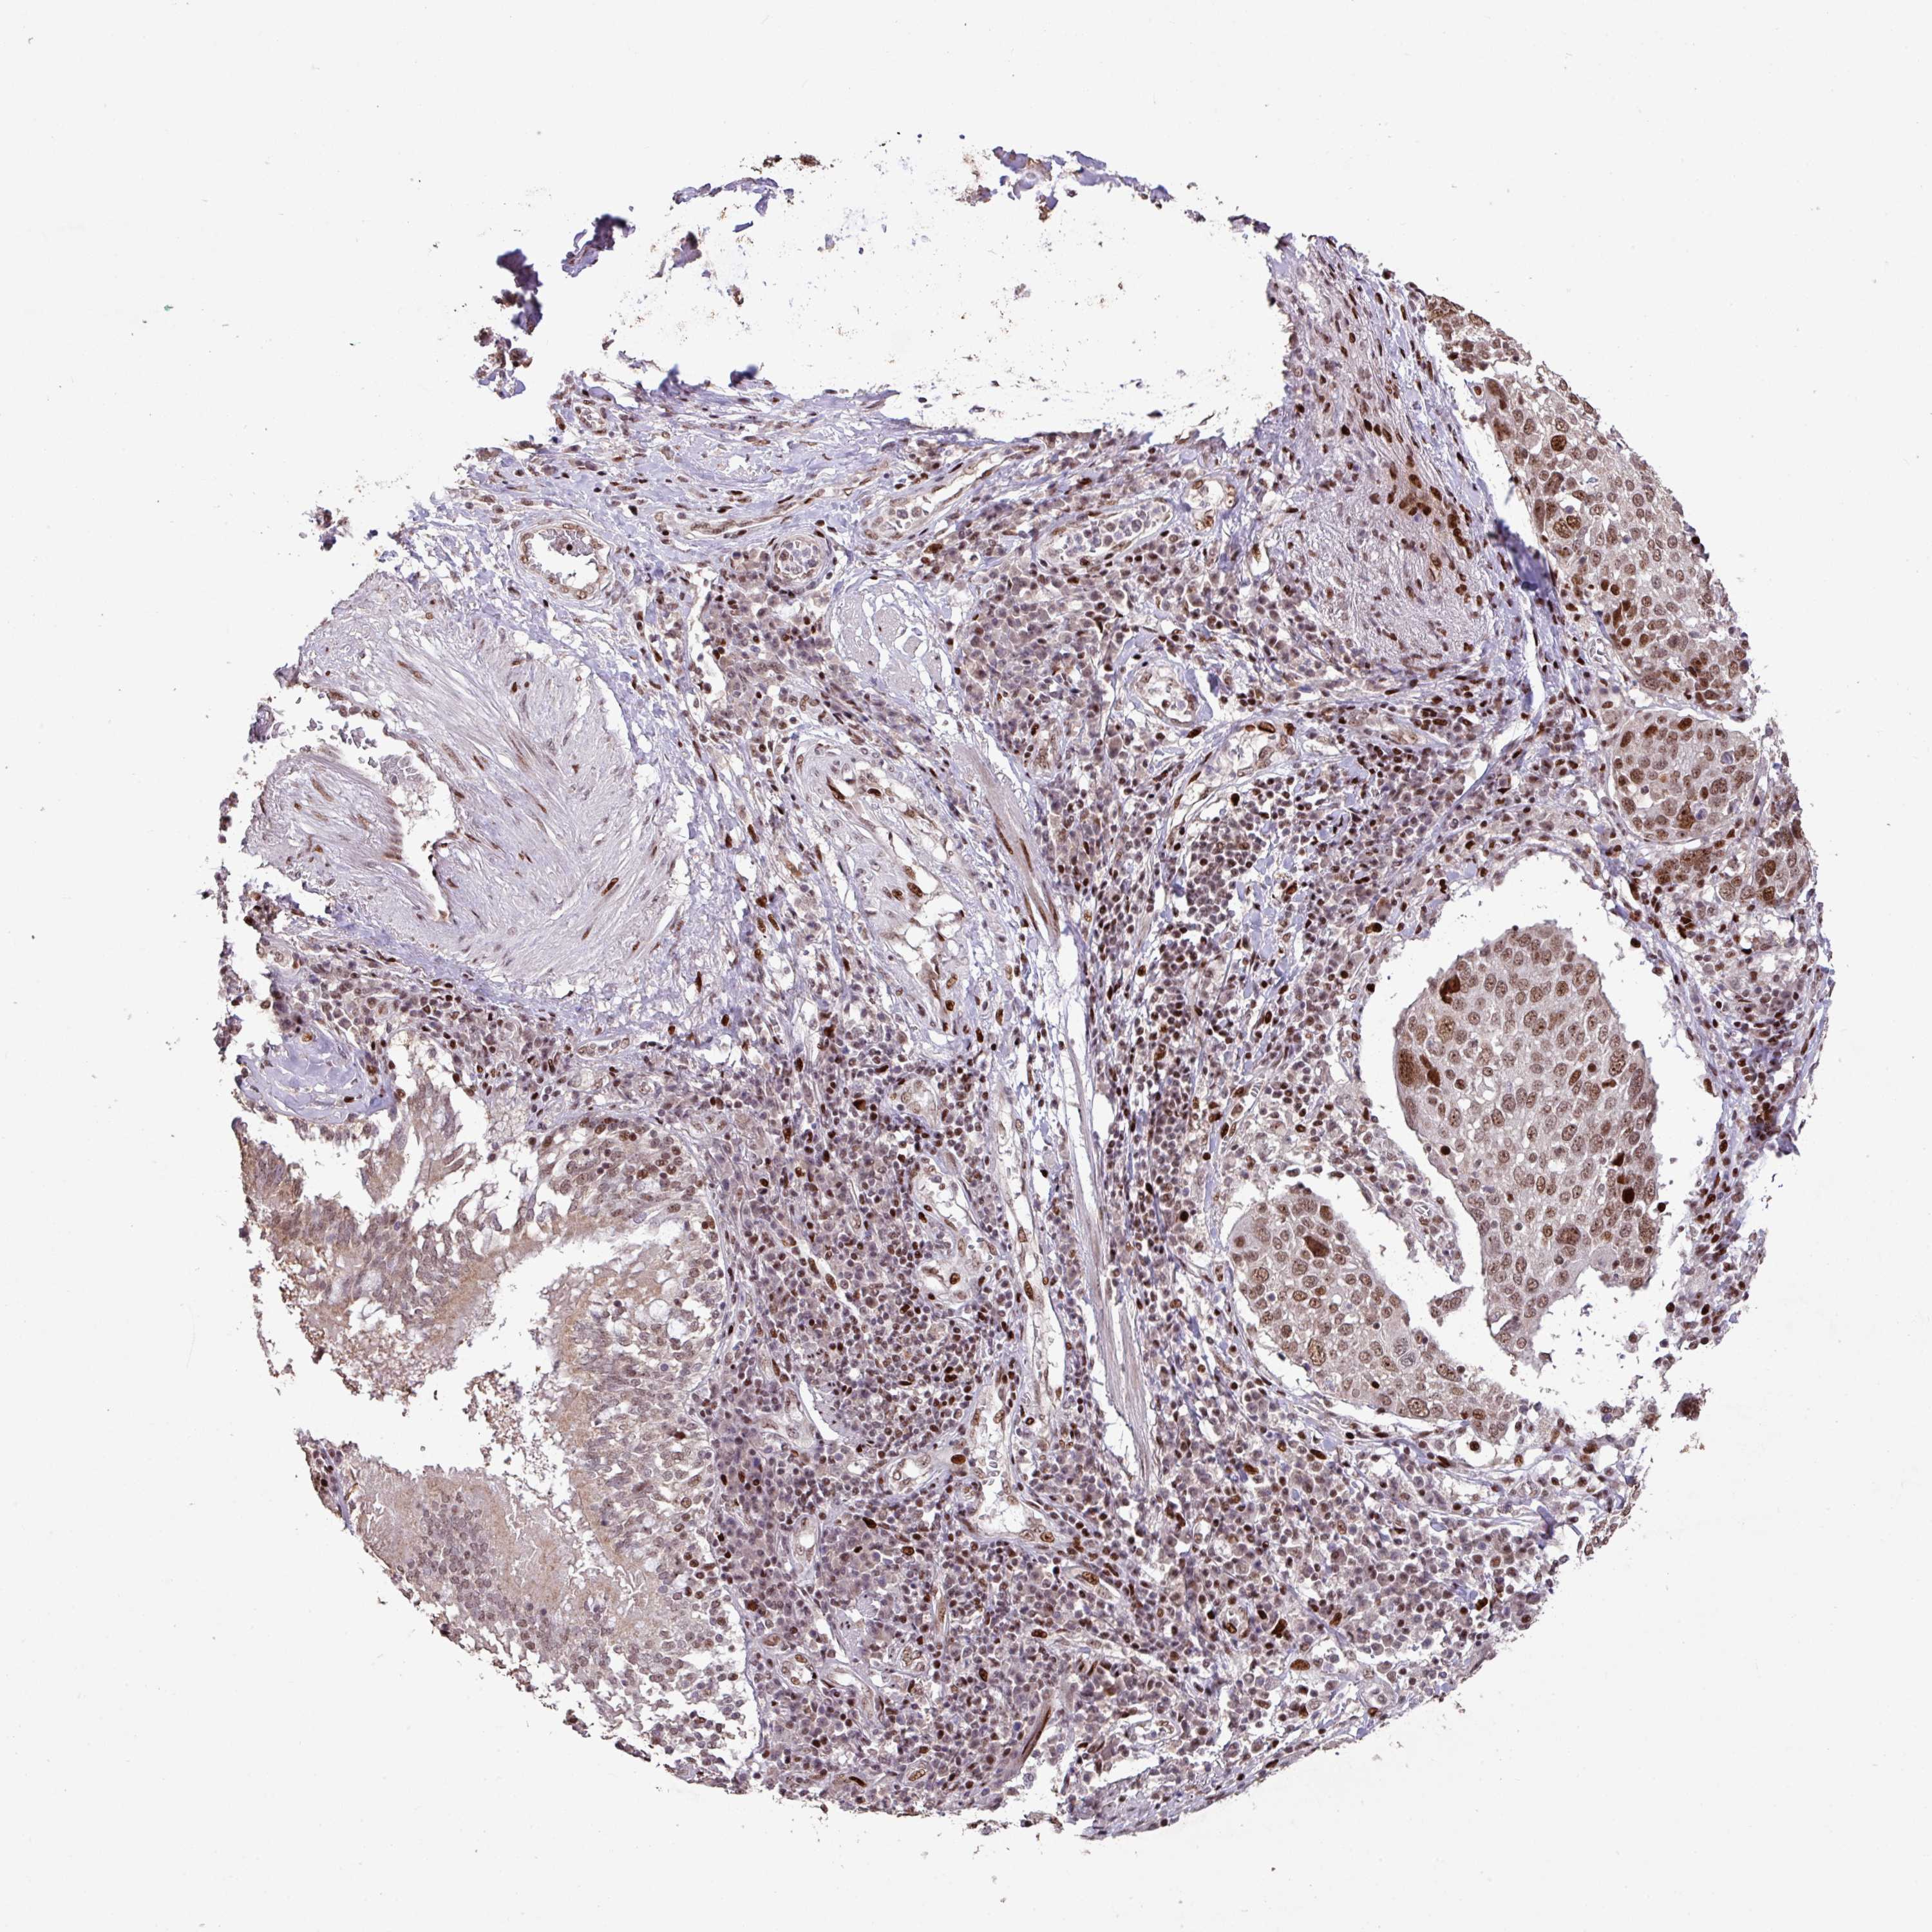

CANCER LUNG CANCER Show tissue menu

LUAD TCGA LUAD VALIDATION LUSC TCGA LUSC VALIDATION PROTEIN LUAD CPTAC PROTEIN LUSC CPTAC PROTEIN EXPRESSION

LUNG ADENOCARCINOMA (TCGA) - Interactive survival scatter ploti

The Survival Scatter plot shows the clinical status (i.e. dead or alive) for all individuals in the patient cohort, based on the same data that underlies the corresponding Kaplan-Meier plots. Patients that are alive at last time for follow-up are shown in blue and patients who have died during the study are shown in red.

The x-axis shows the expression levels (FPKM) of the investigated gene in the tumor tissue at the time of diagnosis. The y-axis shows the follow-up time after diagnosis (years). Both axes are complimented with kernel density curves demonstrating the data density over the axes. The top density plot shows the expression levels (FPKM) distribution among dead (red) and alive patients (blue). The right density plot shows the data density of the survived years of dead patients with high and low expression levels respectively, stratified using the cutoff indicated by the vertical dashed line through the Survival Scatter plot. This cutoff is automatically defined based on the FPKM cutoff that minimizes the p-score. The cutoff can be changed by dragging the vertical line or by entering a cutoff value in the square labeled "Current cut-off".

Under the Survival Scatter plot the p-score landscape (black curve; left axis) is shown together with dead median separation (red curve; right axis). Dead median separation is the difference in median mRNA expression between patients who have died with high and low expression, respectively. It is calculated as follows: median FPKM expression of dead patients with high expression - median FPKM expression of dead patients with low expression. This is intended to aid the user in visually exploring custom cutoffs and the associated p-scores and dead median separation.

Individual patient data is displayed and can be filtered by clicking on one or more of the category buttons on the top of the page. Categories describing expression level and patient information include: high, low, alive, dead, female, male and tumor stages. The scale of the x-axis can be toggled between linear and log-scale by clicking on the "x log" button. Mouse-over function shows TCGA ID, patient information and mRNA expression (FPKM) for each patient.

& Survival analysisi

Kaplan-Meier plots summarize results from analysis of correlation between mRNA expression level and patient survival. Patients were divided based on level of expression into one of the two groups "low" (under cut off) or "high" (over cut off). X-axis shows time for survival (years) and y-axis shows the probability of survival, where 1.0 corresponds to 100 percent.

ZNF709 is potential prognostic, high expression is favorable in Lung Adenocarcinoma (TCGA)

Best expression cut offi

Based on the FPKM value of each gene, patients were classified into two groups and association between prognosis (survival) and gene expression (FPKM) was examined. The best expression cut-off refers the FPKM value that yields maximal difference with regard to survival between the two groups at the lowest log-rank P-value. Best expression cut-off was selected based on survival analysis .

: 0.67

P scorei

Log-rank P value for Kaplan-Meier plot showing results from analysis of correlation between mRNA expression level and patient survival.

N/A

5-year survival highi

5-year survival for patients with higher expression than the expression cutoff.

5-year survival lowi

5-year survival for patients with lower expression than the expression cutoff.

TCGA RNA samplesi

RNA-seq data is reported as average FPKM (number Fragments Per Kilobase of exon per Million reads), generated by the The Cancer Genome Atlas (TCGA) .

Normal distribution across the dataset is visualized with box plots, shown as median and 25th and 75th percentiles. Points are displayed as outliers if they are above or below 1.5 times the interquartile range. FPKM values of the individual samples are presented next to the box plot.

Average pTPM 1.0

Number of samples 497